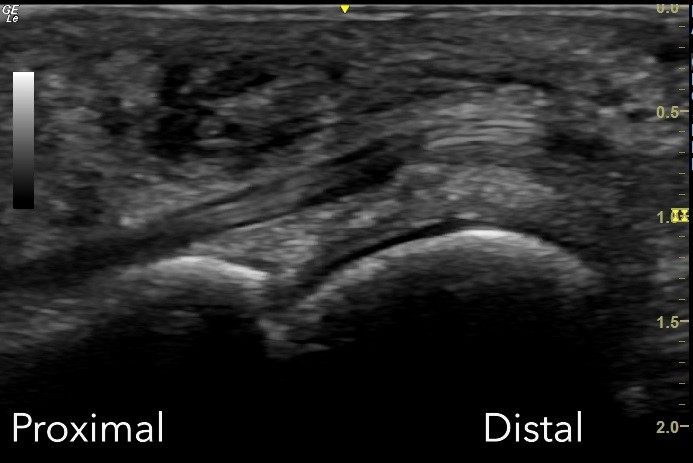

Unlabeled Long Axis view of the plantar first metatarsophalangeal joint.